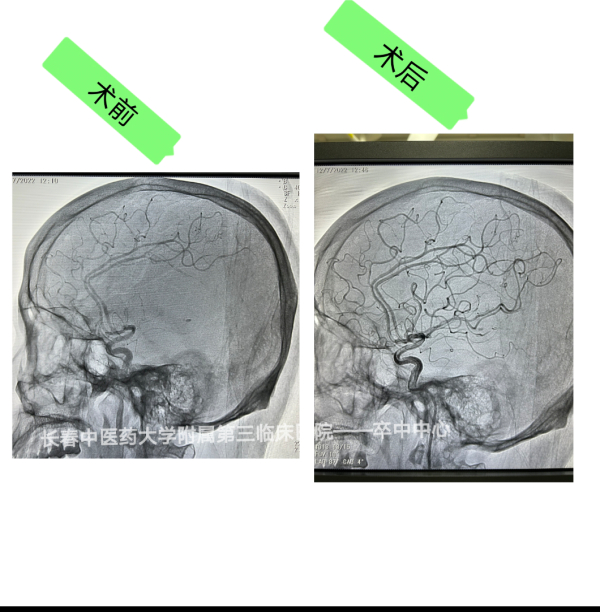

日前,该院卒中中心成功完成首例急性期脑梗死动脉溶栓+脑动脉腔内取栓手术,这也标志该院缺血性脑血管病介入治疗水平迈上新台阶。

随后,脑卒中团队决定急诊动脉取栓应是最佳治疗方案,全体相关人员立即行动,导管室准备、患者术前准备、家属沟通、麻醉评估等工作有条不紊展开,患者在短时间内被推入导管室,在吉林大学中日联谊医院神经外一科于伟东教授和该院多学科共同协作下手术顺利进行。造影证实左侧大脑中动脉起始处完全闭塞,该部位完全闭塞患者往往遗留严重后遗症、甚至死亡,医务部舒遵华主任全程巡视,排除隐患,严保医疗质量安全关,促进团队协作发展。该院介入团队医护人员积极、密切配合,手术护士身穿铅衣在导管室内辅助手术,麻醉医生及时给予镇痛麻醉,于伟东教授、郑军主任、贾世民医生严密配合无缝对接,术中克服各种困难,手术终于顺利完成。

术后当日患者转入ICU观察治疗,次日患者一般状态平稳,精神清醒,脱离危险。转入脑病康复中心进行后续康复治疗。目前,患者运动功能和语言功能已恢复。